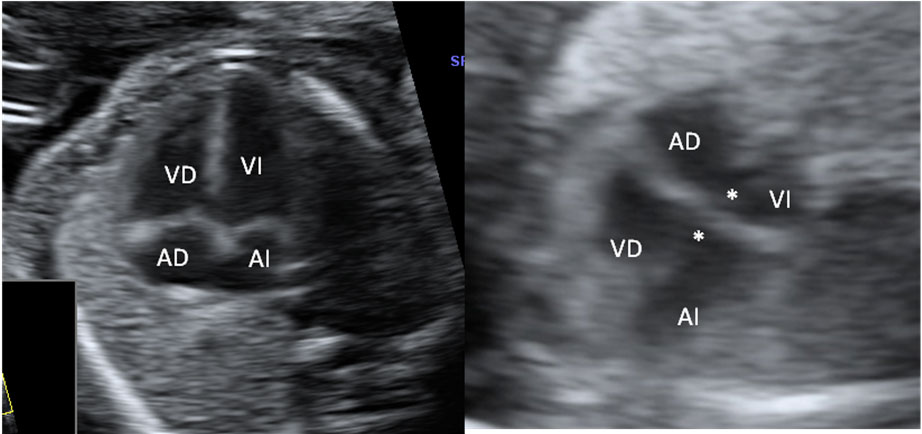

La imagen ecográfica muestra las cuatro cámaras de un corazón normal a la izquierda y de uno con canal atriventricular común (*) a la derecha.